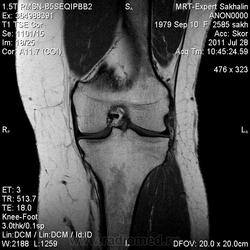

Коленный сустав

Подглядела случай у коллеги.

Что это может быть?

Не вижу криминала. А на что жалуется девушка?

P.S. В костях - это, скорее всего, резидуальный красный костный мозг.